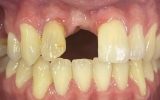

One of the standout contributions of the seminar was the clinical poster presented by Nino Kneževič, featuring a patient treated at Center Hočevar.

The poster provided a clear and structured overview of the pre-, intra-, and postoperative stages of ceramic implant placement, illustrating:

the dynamics of soft- and hard-tissue healing,

and the long-term functional and aesthetic outcomes achievable with ceramic implants.